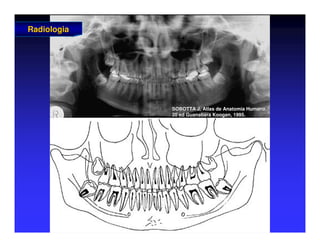

Panorâmica

Radiologia